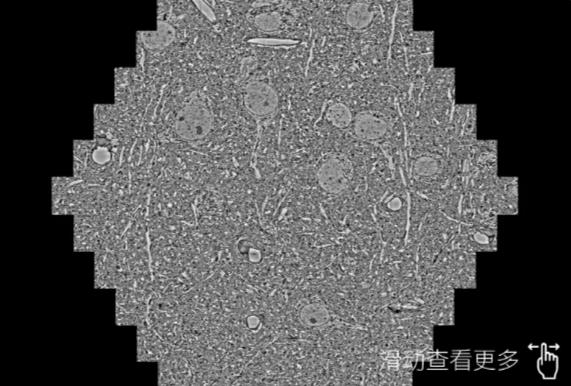

鼠脑切片。左图使用西安蔡司西安扫描电镜MultiSEM706对165μmx143pm面积区域成像,耗时仅需1.5秒。右图为鼠脑切片中30μm区域放大效果。样品由芝加哥大学B.Kasthuri提供。

使用蔡司高速西安扫描电镜MultiSEM对1mm²人脑皮层组织进行高分辨成像,并对其中的各种细胞结构进行三维重构分析。左图展示了2x3mm²组织平面中锥体神经元的三维重构效果。右图显示了局部体积神经元三维重构。图像由哈佛大学chtman实验室提供,渲染图由D. Berger 制作。